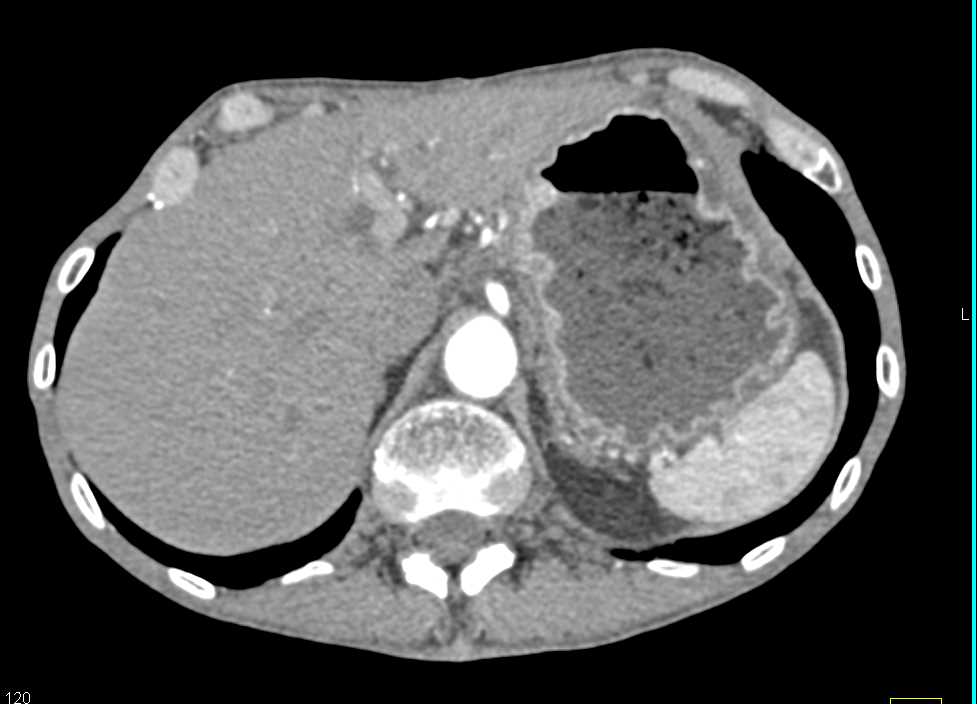

Bulky Gastric Adenocarcinoma with Adenopathy